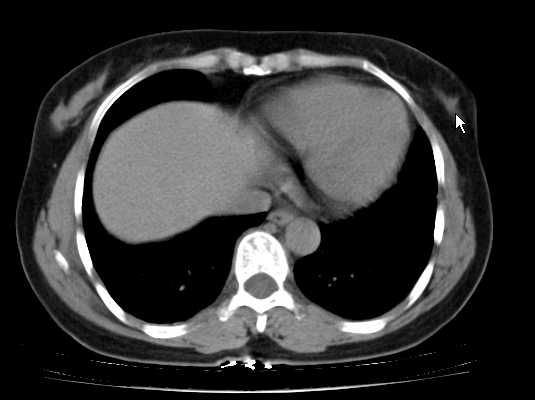

标题: CT25227:背部疼痛伴双侧胸壁痛2月,食欲差。 [打印本页]

标题: CT25227:背部疼痛伴双侧胸壁痛2月,食欲差。

肺结核并胸椎结核?请各位高手指教。

用椎体的条件来扫胸椎呀!考虑1左侧胸膜小结节形成2椎体结核并冷脓肿形成

考虑胸椎结核并椎旁软组织肿胀。

左肺结核灶,胸椎结核并冷脓肿。

左肺结核灶,胸椎结核并冷脓肿

椎旁软组织肿胀。